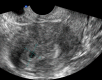

Figure 1

Echographie de la grossesse intra-utérine